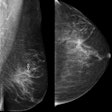

Can deep learning power mammography CAD to new heights?

Large U.K. study gets specific on breast ultrasound

Multiparametric MRI shines for suspected breast cancer